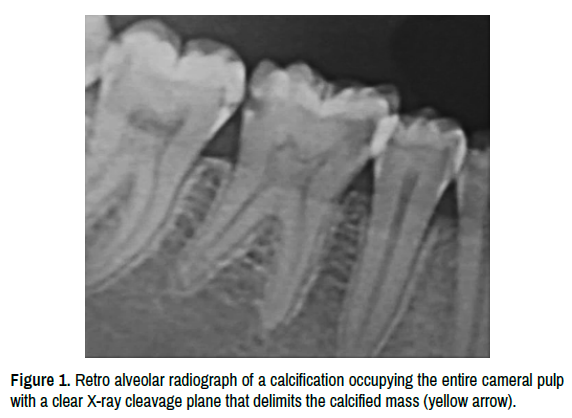

A 22-year-old patient in good general condition consulted following spontaneous pain related to the first left mandibular molar. The clinical examination reveals a Sista 1.3 carious lesion. The radiological examination shows the presence of calcification which obliterates almost all of the pulp chamber with a cleavage plane (clear X-ray line) between the calcified tissue and the healthy dental tissue (Figure 1). After carious eviction and opening of the access cavity by connecting the projection of the pulp horns (Figure 2), the extent of the pulpolite is delimited by a hemorrhagic colorimetric demarcation between the dentin of the cameral walls and the calcified tissue center (Figure 3). Subsequently, this demarcation was widened using an ultrasonic diamond insert (ET18D) (Figure 4). Once released and mobilized, the calcified mass is completely removed by an endodontic excavator (Figures 5-7). After removal of the pulpstone, abundant irrigation with Naocl 5.25% was performed to better visualize the root canal entries (Figure 8) and from here endodontic treatment was continued as if of a normal tooth without particularities (Figure 9).

Figure 1. Retro alveolar radiograph of a calcification occupying the entire cameral pulp with a clear X-ray cleavage plane that delimits the calcified mass (yellow arrow).